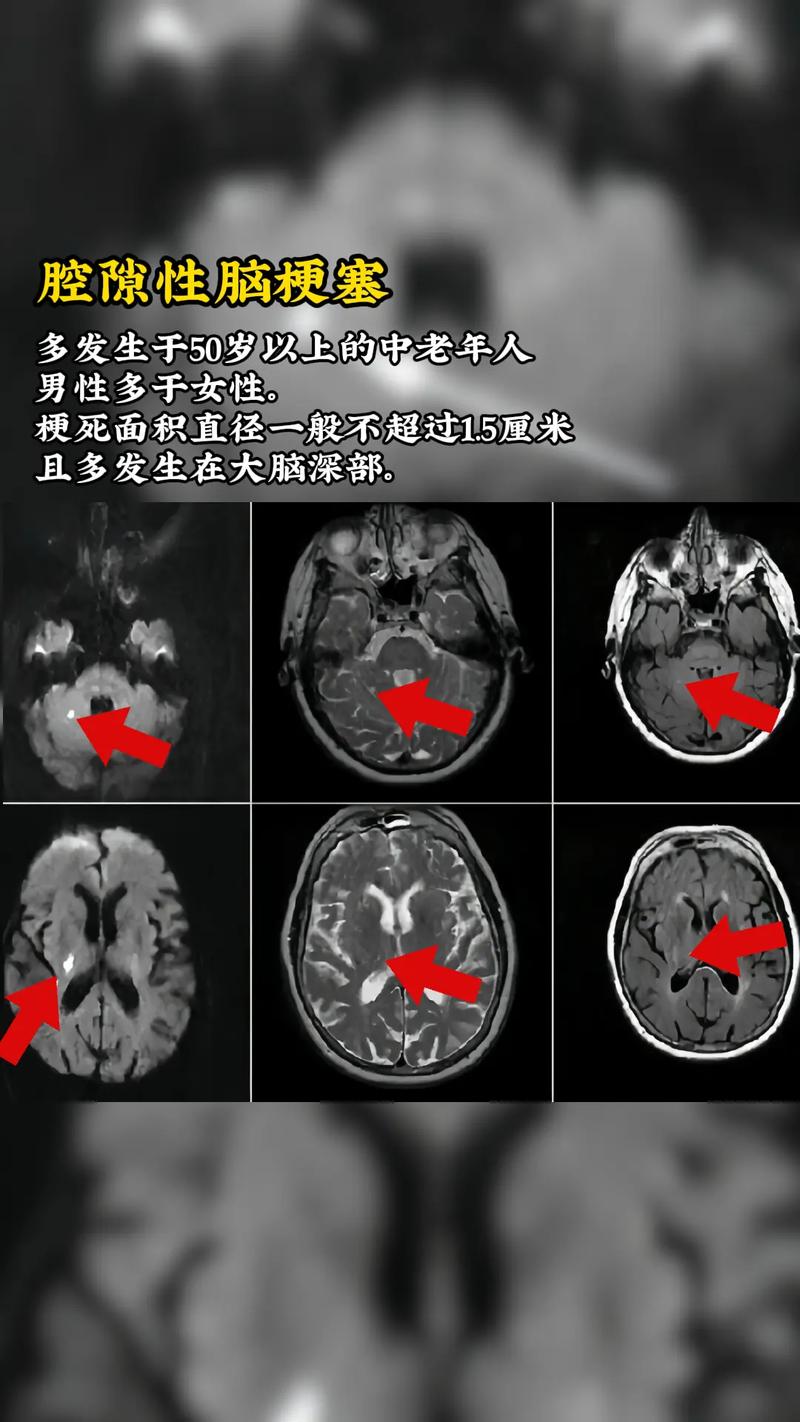

MRI(磁共振成像):

- 急性期脑梗塞: 对早期梗塞非常敏感,几小时内就能发现,表现为T2加权像和FLAIR像上高信号(发白),DWI像上高信号(发白),这是诊断急性脑梗塞的金标准。

- 慢性期脑软化灶: 表现为T1加权像上低信号(发黑),T2加权像和FLAIR像上高信号(发白),其内信号均匀,像脑脊液。